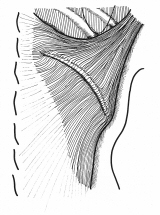

壁細胞。休止状態と分泌状態

どこかの国際学会でスライドに使っていただいたようです。確か一枚目を描くのに5時間、二枚目が3時間かかりました。